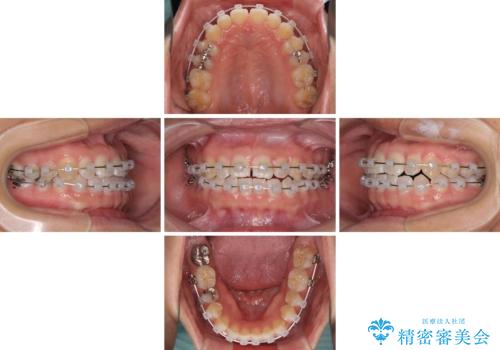

- クリアブラケット

- 9ヶ月

- 5-10回

下の前歯が上の前歯を突き上げるように咬合するため、咬み合わせの位置を改善しながら隙間を閉じていきました。